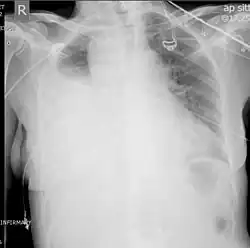

Chest X-ray

A chest X-ray is the most common technique used to diagnosis a hemothorax.[23] X-rays should ideally be taken in an upright position (an erect chest X-ray), but may be performed with the person lying on their back (supine) if an erect chest X-ray is not feasible. On an erect chest X-ray, a hemothorax is suggested by blunting of the costophrenic angle or partial or complete opacification of the affected half of the thorax. On a supine film the blood tends to layer in the pleural space, but can be appreciated as a haziness of one half of the thorax relative to the other.[5] A small hemothorax may be missed on a chest X-ray as several hundred milliliters of blood can be hidden by the diaphragm and abdominal viscera on an erect film. Supine X-rays are even less sensitive and as much as one liter of blood can be missed on a supine film.[24]